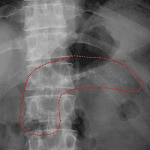

Age: 44

Sex: Male

Indication: Abdominal pain

Findings

- No evidence of acute cardiopulmonary disease

- Nonobstructive bowel gas pattern

- No free subdiaphragmatic air

- Pancreatic calcifications

- Lumbarized S1 vertebral body with spina bifida occulta

Diagnosis

- Pancreatic calcifications

No evidence of acute cardiopulmonary disease.

Nonobstructive bowel gas pattern.

No evidence of pneumoperitoneum.

Pancreatic calcifications, compatible with sequela of chronic pancreatitis.